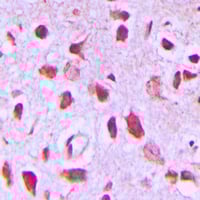

IHC (Immunohistochemistry)

(AAA327530 at 1/100 staining Human brain cancer tissue by IHC-P. The sample was formaldehyde fixed and a heat mediated antigen retrieval step in citrate buffer was performed. The sample was then blocked and incubated with the antibody for 1.5 hours at 22 degree C. An HRP conjugated goat anti-rabbit antibody was used as the secondary.)